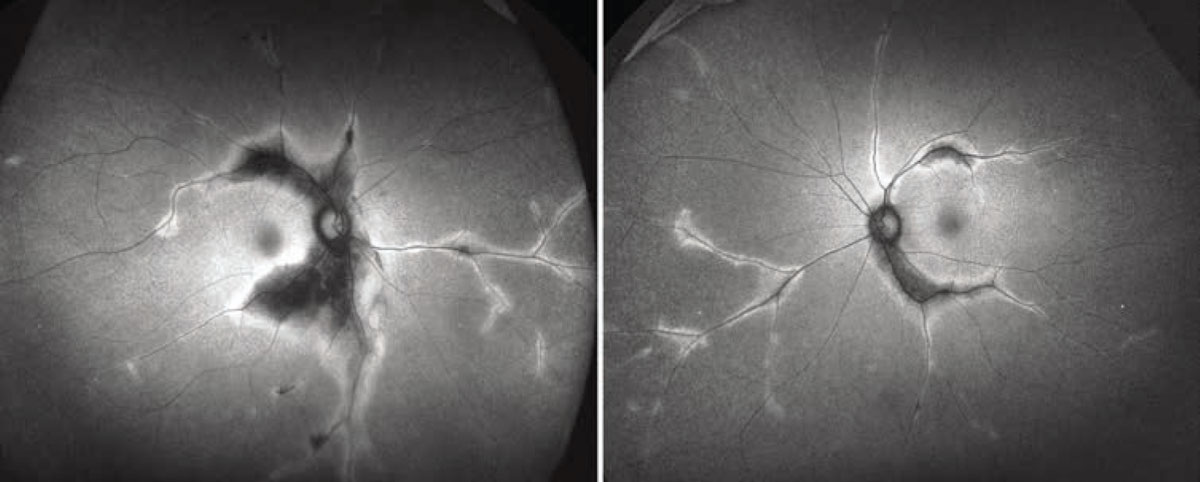

We also obtained widefield fluorescein angiography. Early frames revealed normal arterial and venous filling times with scattered microaneurysms and areas of peripheral capillary dropout, consistent with subclinical nonproliferative diabetic retinopathy. Large areas of hyperfluorescence, consistent with window defects, were seen along the proximal arcades (Figures 4A,B). Late frames demonstrated patchy interstitial leakage in the macula and periphery with persistent window defects and/or staining in the regions of fundus pigmentary changes (Figures 4C,D). Hyperpigmented clumps corresponded to signal blockage on the angiogram. No disc or vascular leakage was apparent in either eye.

Figure 4. Early-to-mid frames of widefield fluorescein angiography of the right (A) and left (B) eye show clear window defects in the areas of fundal hypo-pigmentation, with intact arterial and venous filling. Late frames (C and D) reveal persistent window defects and staining. Background nonproliferative diabetic retinopathy and subclinical macular edema are also seen in both eyes. |